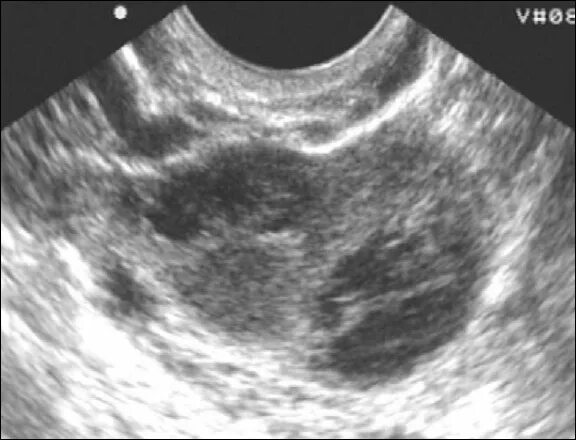

Сальпингит и оофорит что это